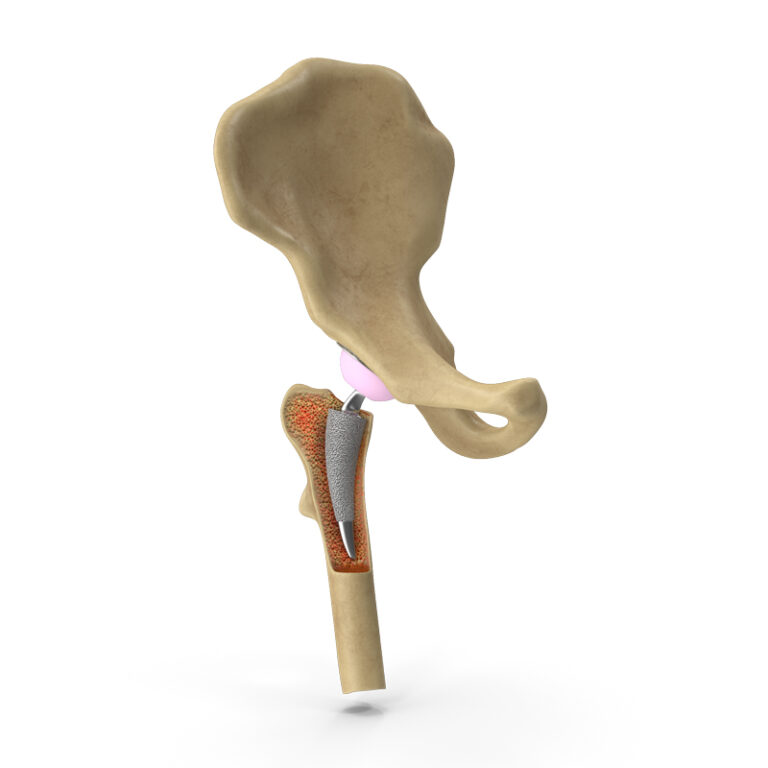

También conocida como cirugía de reemplazo total/parcial de cadera, cirugía de reemplazo articular de cadera o colocación de prótesis de cadera. Consiste en la eliminación del cartílago y huesos dañados de su cadera, para posteriormente colocar una prótesis total/parcial de cadera.

Al reemplazar una articulación dañada por una prótesis articular, el dolor desaparece o disminuye de forma considerable en la mayoría de los casos, mejorando su calidad de vida.

Una artroplastia de cadera tiene una duración de 2 a 3 horas, esto dependiendo de si existen lesiones o malformaciones asociadas que también requieren de reparación.

Los beneficios de la artroplastia de cadera incluyen mejoría o desaparición del dolor después de la cirugía, mejoría en la movilidad de la cadera afectada y mejoría en la calidad de vida.